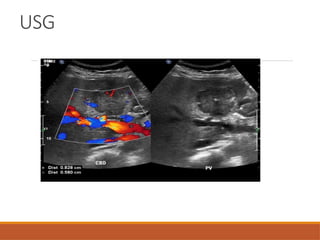

USG

Typically well defined, homogeneous & hyper- echoic

lesions(67%-79%).

May be hypoechoic, within background of fatty liver.

Post acoustic enhancement.

Giant hemangioma -heterogeneous with central hypo -

echoic foci.

Subtle iso-echoic mass with contour abnormality.

Displacement of vascular structure.

Central scar- hypo-echoic linear or stellate

area, may be hyper-echoic.

Doppler study: well developed peripheral & central blood

vessels are seen.

USG Typically well defined,homogeneous & hyper- echoic lesions(67%-79%). May be hypoechoic, within background of fatty liver. Post acoustic enhancement. Giant hemangioma -heterogeneous with central hypo - echoic foci.

USG Subtle iso-echoic masswith contour abnormality. Displacement of vascular structure. Central scar- hypo-echoic linear or stellate area, may be hyper-echoic. Doppler study: well developed peripheral & central blood vessels are seen.

• #12 Grey scale usg image showing well defined hyperecheic lesion in segment 6 of right lobe Axial cect image in portal veous phase showing giant hemangioma in left lobe of liver with peripheral nodular enhamncement

• #18 Grey scale usg image showing a well defined isodense mass in segment 7 of right lobe on doppler interrogation there is a stellate pattern of blood vessel arrangement